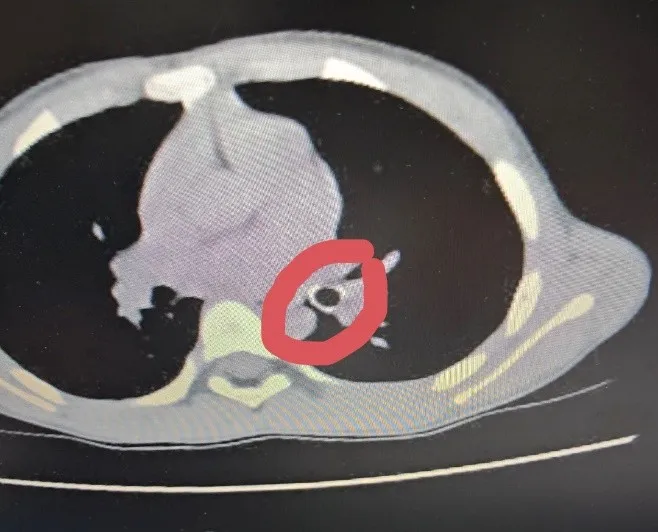

Khi nhập viện, em Đ. tỉnh táo nhưng ho nhiều, khò khè, thở nhanh, thông khí phổi giảm. Qua thăm khám và chẩn đoán hình ảnh, các bác sĩ xác định trẻ bị hóc dị vật đường hô hấp. Dị vật nằm sâu trong phế quản, gây cản trở thông khí. Sau hội chẩn, bệnh nhi được chỉ định nội soi phế quản cấp cứu để lấy dị vật. Thủ thuật được thực hiện an toàn, dị vật là đầu ngòi bút nhựa được lấy ra hoàn toàn. Sau can thiệp, tình trạng hô hấp của trẻ cải thiện rõ rệt và tiếp tục được theo dõi, điều trị tại bệnh viện.

Dị vật là đầu ngòi bút nhựa